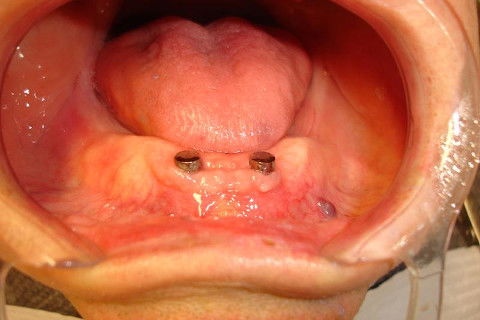

Após exodontia, instalação dos implantes imediatos e abutments magnéticos. Cirurgia realizada por Dr. Angelo Menuci Neto.

Abutment com Attachment Magnético Ankylos.

Já após cicatrização , os abutments magnéticos instalados sobre os implantes.